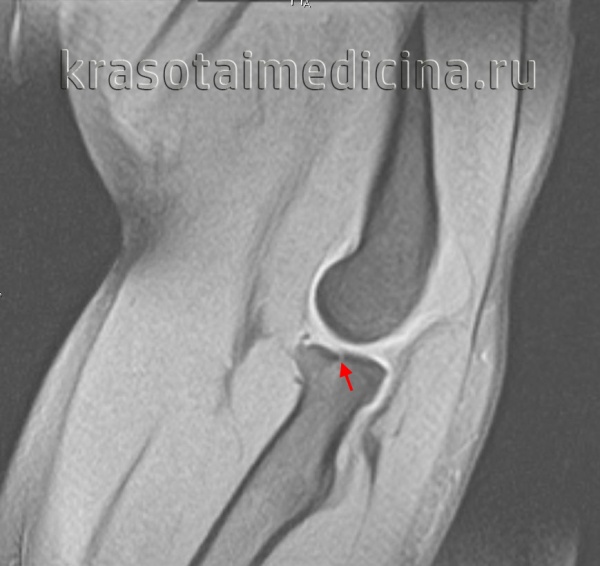

50% этих переломов являются внутрисуставными, могут сопровождаться повреждением дистального радиоульнарного сочленения, в 40 % случаев встречается повреждение триангулярного хряща, в 30% повреждение ладьевидно-полулунной связки, в 15% случаев полулунно-трёхгранной связки.

Повреждение сопровождается резкой болью, отеком и кровоизлияниями. Возможна крепитация и патологическая подвижность. При смещении выявляется видимая деформация чуть выше сустава или в его проекции. Движения и пальпация резко болезненны. Диагноз подтверждают по результатам рентгенографии лучезапястного сустава. При сложных переломах и в ходе предоперационной подготовки может потребоваться проведение КТ лучезапястного сустава и МРТ. Лечение в подавляющем большинстве случаев консервативное.

Рентгенография лучезапястного сустава. Перелом дистального метаэпифиза лучевой кости со смещением отломков.